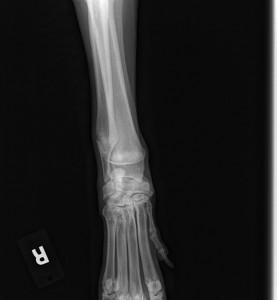

2) He is collapsed in the pasterns and flat footed, bad hips, eastie westie, swollen legs/feet

The Vet watched him gait prior to sedation and his hips and gait is really wonky. It is too early to do proper x-rays on his hind end to determine a lot but, under sedation, his Vet got a great look at manipulating his hips and joints and no crepitus noted at this time.

With his collapsed pasterns, flat feet etc. the Ester C should help greatly. With good nutrition, proper vet care and exercise, we should see marked improvement yet, he is a victim to bad genetics(breeding), and sadly, neglected/abused.